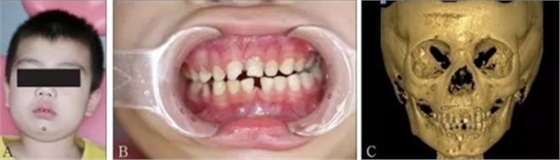

頜面部上下頜骨、顴骨及顴弓骨折、骨折片移位壓迫咀嚼肌群和下頜骨喙突,影響下頜骨的活動而造成張口受限[10-12](圖 9、10)。

A:患者面像;B:口內像;C:三維成像;D:全景片;E:冠狀位。

圖 9 面部外傷